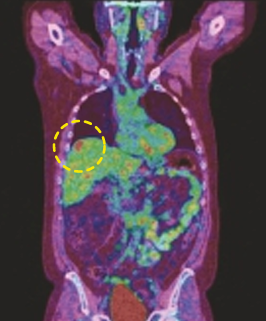

CASE [PET-CT Fusion]

15 min (50%) Scan Without Denoising

15 min (50%) Scan With Denoising

30 min (100%) Scan Standard